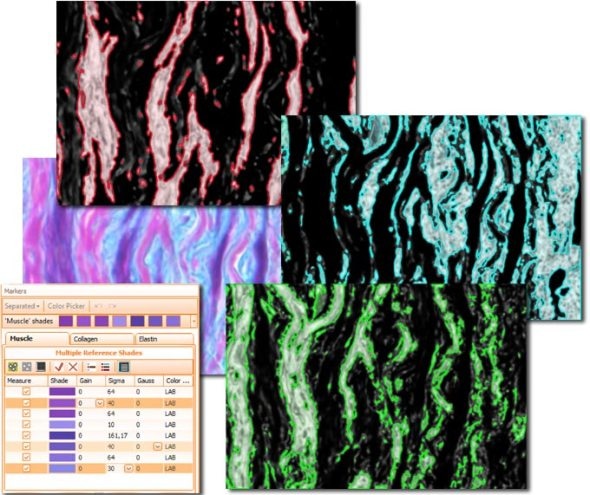

The second color separation algorithm is semi-manual (using a color picker) and separates an unlimited amount of colors with great control and precision (see image with muscle, collagen and elastin detection below).

The Total Area algorithm segments stained areas in a sample (see Muscle/Collagen/Elastin image above).